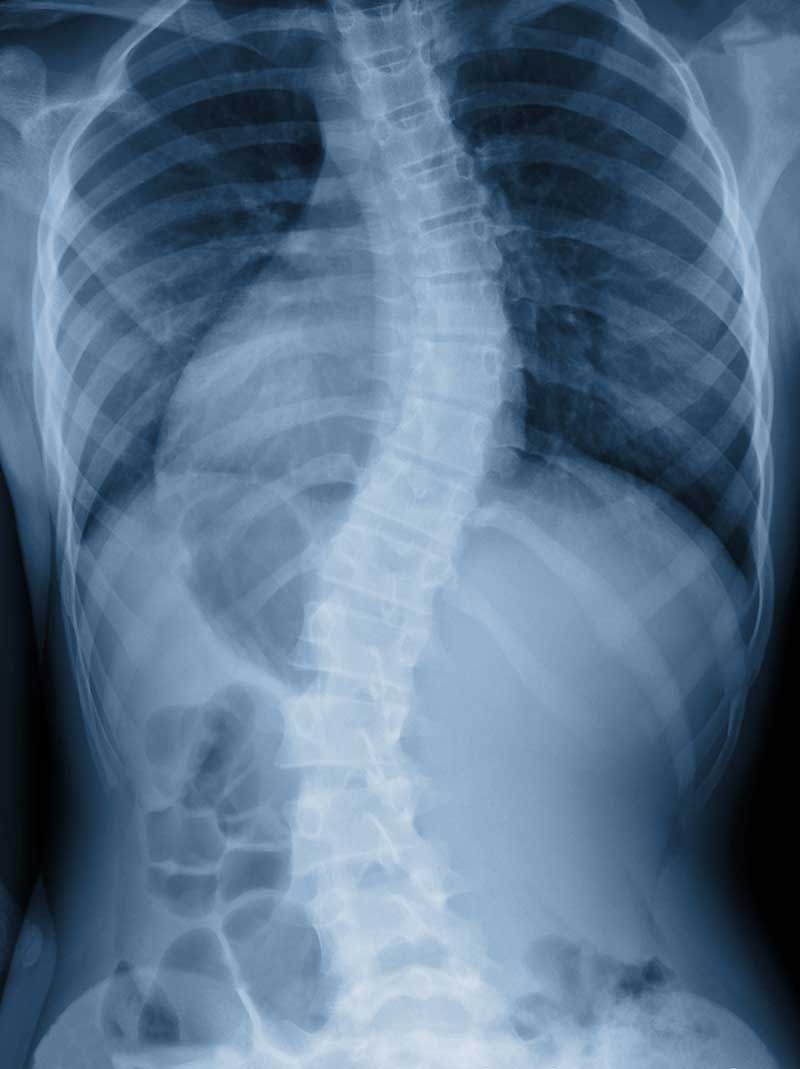

When detected early, scoliosis can be managed and treated to prevent the problem from getting worse. With scoliosis, the spine has abnormal curvatures to the side or even twists. Most cases of scoliosis appear for unknown reasons as scoliosis tends to develop before puberty in adolescence, in children who previously had no spine issues.

- A spine that curves too much to the left or right